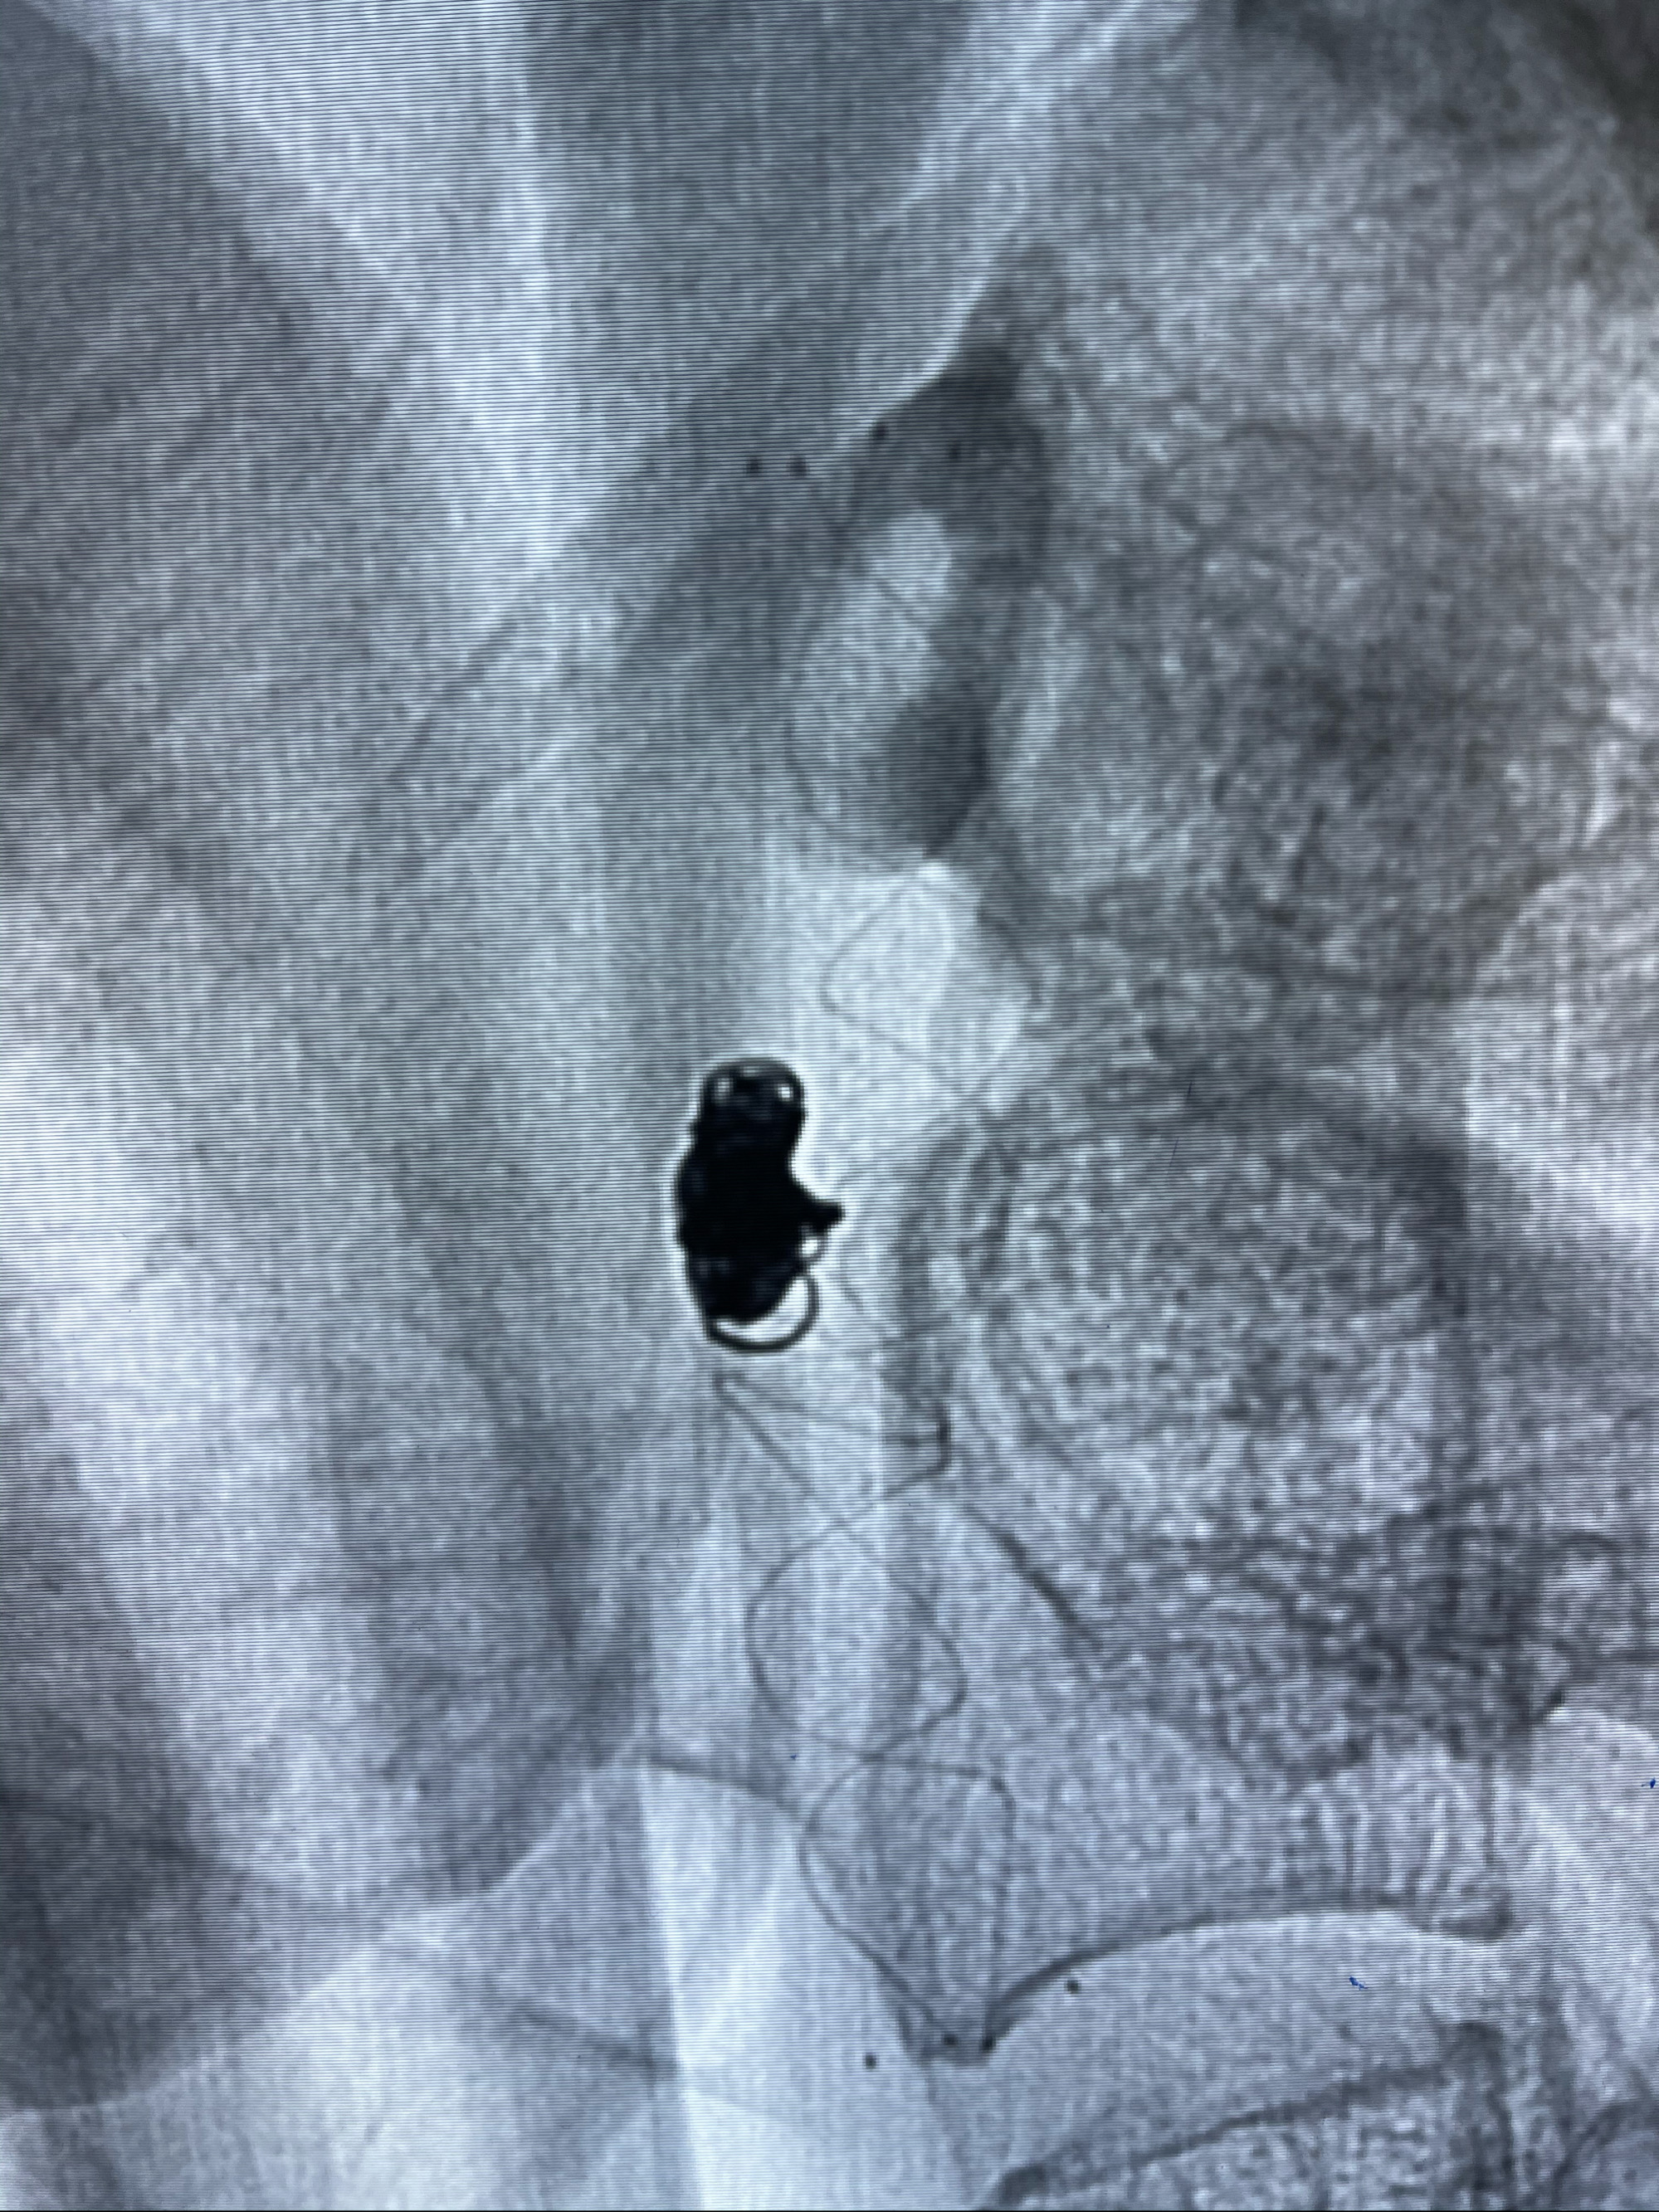

Eterprise4.0-23mm支架导管到位

8mm-40cm微弹簧圈成篮